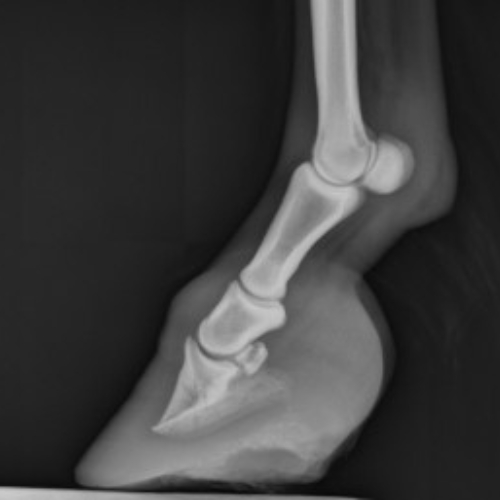

Challenging podiatry cases require close communication between the veterinarian, farrier, and owner. We strongly believe in coordinating the efforts of all parties involved so that the horse receives the best treatment possible. Our digital radiography system makes sharing images easy.

Farrier consultations focus on evaluating and addressing the hoof health of horses. These consultations often include an assessment of hoof structure, balance, and shoeing requirements tailored to the specific needs of the horse. At Arlington Equine, the service also integrates veterinary perspectives, allowing for a more comprehensive approach to your horse’s care.

Farrier consultations may involve corrective shoeing, treatment for lameness, or adjustments to improve gait and posture. The collaborative process ensures that all factors influencing hoof health—such as diet, activity level, and conformation—are considered.